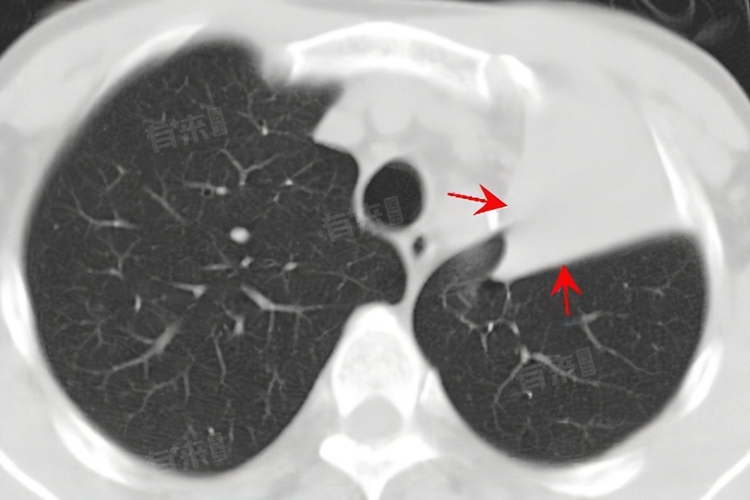

肺萎缩,即肺不张,是指肺的部分或完全无气体状态,导致其体积缩小,进而影响肺功能。这一现象可由多种原因引起例如先天性因素、支气管阻塞、肺部受外压、慢性肺部疾病以及医源性因素等,每种原因对应着不同的治疗方法,包括药物治疗、手术治疗等。